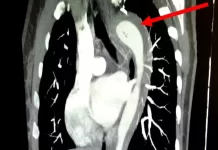

Mulher de 45 anos rompe aorta durante orgasmo e passa por cirurgia

Um caso raro e de alto risco envolvendo a ruptura da aorta foi relatado pelo American Journal of Case Reports. A paciente,...